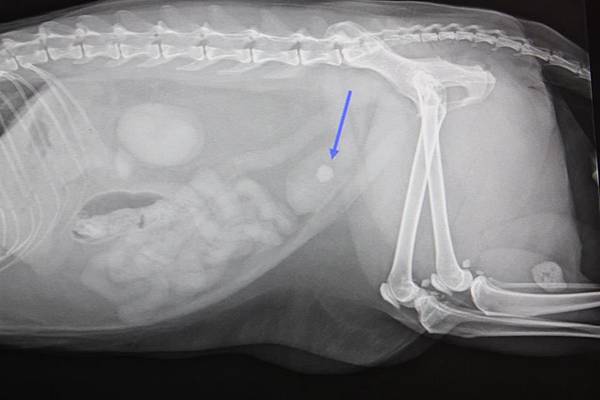

數位影像系統檢查下發現的膀胱結石 (箭頭處)